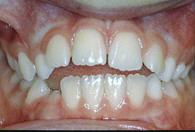

| Unterkieferrücklage | Unterkieferrücklage | |